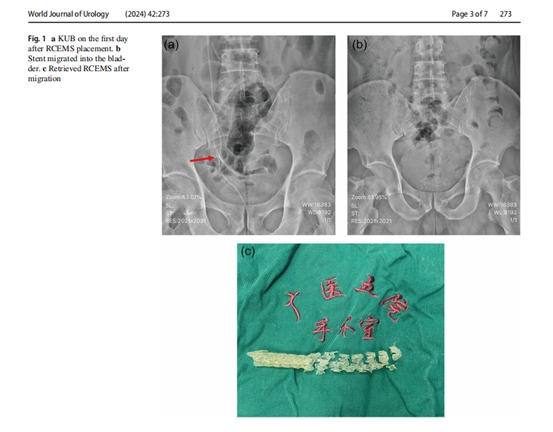

广医五院泌尿外科徐桂彬教授团队致力于输尿管狭窄的整体化治疗,在国内率先开展金属覆膜支架治疗良恶性输尿管狭窄,近6年累计治疗各类输尿管狭窄患者超300例,累积了丰富的临床经验。金属覆膜支架治疗复杂性输尿管狭窄具有创伤小、恢复快的优点,是输尿管狭窄整体治疗化体系的重要组成部分。目前,国内在该领域的研究较少,也缺乏权威、大宗数据分析。团队基于诊疗的大样本临床数据分析,对金属覆膜支架临床应用及移位并发症进行因素分析,得出包括输尿管狭窄长度短、肾积水程度大和球囊扩张为支架移位的高危因素,为金属覆膜支架的临床运用和支架移位风险提供一定的参考作用。